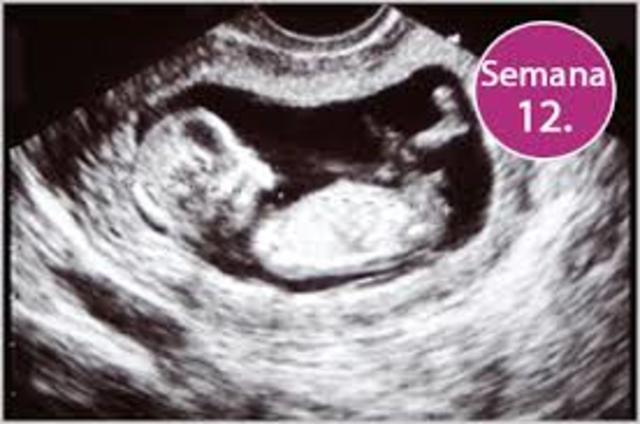

• 12 semanas

12 semanas

Comienza a aparecer el lanugo, que es un vello delicado, en la frente y en los brazos y piernas. La piel adquiere color rojo. Los órganos genitales externos están diferenciados Abre y cierra la boca, lo que hará que trague líquido amniótico, y esto le producirá hipo. Frunce la frente, patea, extiende los dedos de los pies, cierra las manos y puede girar la cabeza.